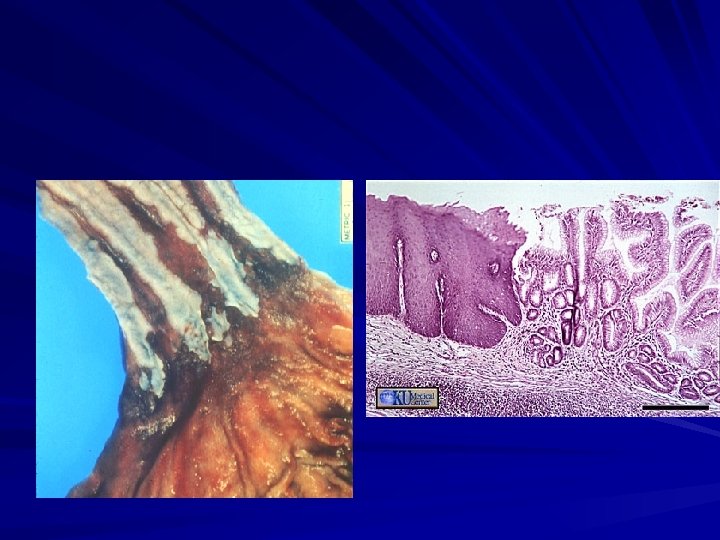

Red, velvety mucosa located between the smooth, pale pink esophageal squamous mucosa and the more lush, light brown gastric mucosa. Microscopically: – the esophageal squamous epithelium is replaced by metaplastic columnar epithelium. – dysplasia (the presumed precursor of malignancy)

Barret’s